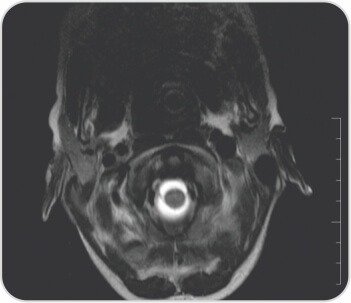

মস্তিষ্কের সাথে পুরো মেরুদণ্ডের এমআরআই দীর্ঘ সেগমেন্টের পূর্ববর্তী এপিডুরাল সংগ্রহ প্রকাশ করেছে যা T2-তে হাইপারিনটেন্স এবং T1-এ হাইপোইনটেন্স ছিল যার লেয়ারিং C2 থেকে D8 স্তর পর্যন্ত প্রসারিত হয়েছে যার ফলে সার্ভিকাল এবং ডোরসাল কর্ডের পশ্চাৎ স্থানচ্যুতি এবং কম্প্রেশন-সম্ভাব্য রক্তক্ষরণ, পোস্টেরিয়র প্যারাস্পাইনাল নরমের মৃদু মচন। সার্ভিকাল অঞ্চলে টিস্যু লক্ষ্য করা গেছে। ল্যাবরেটরি তদন্তে Hb7.5gr%, TLC11, 700/mm3, প্লেটলেট 2.92lakhs/mm3, Rbs 96 mg/dl, সিরাম ক্রিয়েটিনিন 0.5mg%, Bl.urea 37.0 mg%, Serum Na+ 128, S.K, S.3.6+93.0। Cl- 21.90 meq/l মোট বিলিরুবিন 13.70 মিলিগ্রাম% (সরাসরি 8.20 পরোক্ষ 254) SGPT 180u/l SGOT 265.00 u/l Alk ফসফেটেস 6.00, মোট প্রোটিন 2.80 g% (Alb.3.20b.68.0%), 8.0b%। PT 86.8 সেকেন্ড INR > 2.62, APTT 7 সেকেন্ড। HAV IgM অ্যান্টিবডি পজিটিভ: 3; HBsAg, HBeAg, HCV, HIV: প্রতিক্রিয়াশীল নয়; ANA প্রোফাইল নেতিবাচক ছিল। তাকে নিবিড় পরিচর্যা ইউনিটে ভর্তি করা হয়েছিল এবং প্যারেন্টেরাল ভিটামিন কে ইনজেকশন এবং ভেন্টিলেটরি সাপোর্টিভ কেয়ার সহ 3 ইউনিট এফএফপি, 6টি পিআরবিসি পেয়েছিলেন। নিউরো সার্জারির পরামর্শের পরে C2-C5 ল্যামিনোপ্লাস্টি এবং ভর্তির 15 দিনে হেমাটোমা সরিয়ে নেওয়া হয়। 2 তম দিনে, ট্র্যাকিওস্টোমি করা হয়েছিল এবং ধীরে ধীরে ভেন্টিলেটর ছাড়ানো হয়েছিল। পুনর্বাসন কেন্দ্রে বিপ্যাপের সহায়তায় 2.90 তারিখে তাকে ছেড়ে দেওয়া হয়েছিল। কোয়াড্রিপ্লিজিয়া স্রাবের সময় উপরের অঙ্গে গ্রেড 157 শক্তি এবং মোট বিলিরুবিন 68 mg/dl, SGPT 2, SGOT XNUMXu/l সহ টিকে ছিল। দুই সপ্তাহের ফলো-আপে তিনি স্পাস্টিক কোয়াড্রিপ্লেজিয়া - সমস্ত অঙ্গে গ্রেড XNUMX শক্তি, স্থিতিশীল হেমোডায়নামিক্স এবং স্বাভাবিক লিভার ফাংশন পরীক্ষায় আরও উন্নতি করেছেন।